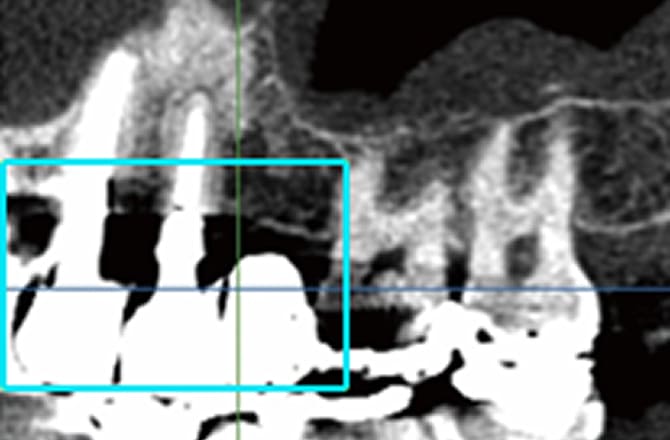

2.金属の影響を除去

-

口の中は体の他の部分とは違い、歯の詰め物や被せものとして金属があります。金属はX線を通しにくいため、その影響でこれまでのCTでは周りの骨の状態が把握できないことがありました。

当院の歯科用CTは金属の影響を除去するプログラムを搭載していますので、他のCTでは金属の影で映らない部分の骨でも診断することができます。 -

これまでのCT:金属の周りが黒くなり映っていません。

当院の歯科用CT:金属の周りでも骨の状態を診断できます。